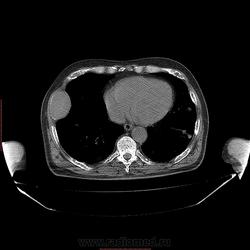

Пациент 1946 г.р., состоит на Д учете в онкодиспансере по поводу с-ч кожи (базалиома), прошел курс лучевой терапии, в 2009г на Ргенографии выявили образование 7 ребра, направили на Кт, на КТ (2009г) был выставлен д-з ГКО, пункционная биопсия не произведена. А сейчас вот такая картина, с множественными литическими очагами в костях грудного склета + образование 7 ребра, с отрицательной динамикой.

повторно взяли пациента, сняли кости таза, такая же картина- множественные очаги литической деструкции. Заключение: больше данных за миеломную болезнь.